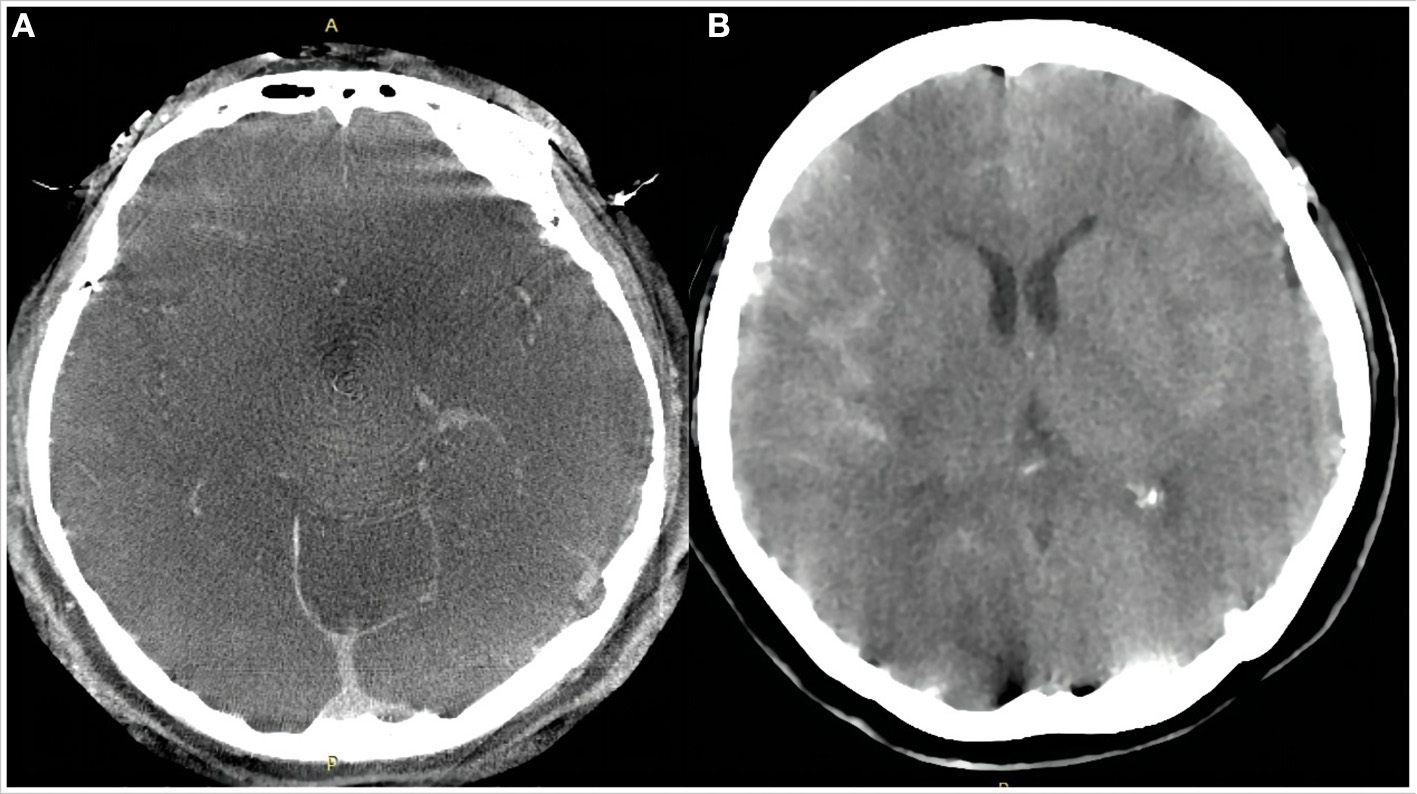

Figure 2

Dyna computed tomography immediately after the procedure (A) showed no subarachnoid hemorrhage or intracerebral hemorrhage. Emergency head computed tomography 11 h after the procedure (B) showed a small amount of hemorrhage in the Sylvian cistern, anterior interhemispheric cistern, and lateral ventricle.

Dual antiplatelet treatment (aspirin 100 mg daily and clopidogrel 75 mg daily) was initiated 5 days before the endovascular procedure. Platelet function was assessed by standard light transmittance aggregometry to measure platelet aggregation. Light transmittance aggregometry was conducted using platelet-rich plasma by the turbidimetric method in a 4-channel aggregometer (AG800; Techlink Biomedical, Inc, Beijing, China). Maximal platelet aggregation (MPA) was defined as the percentage change in light transmittance. The testing results showed that the MPA of ADP and arachidonic acid (AA) was 43.8 and 6.7%, respectively, suggesting that the platelet function of this patient was in a safe interval before therapeutic procedure. Under general anesthesia, a 6F 115 cm Navien (Covidien, Irvine, California, USA) intracranial support catheter assisted by a 6F 90 cm Neuron Max 088 sheath (Penumbra, Alameda, California, USA) was advanced into the right ICA. Under roadmap guidance, a 0.027-inch 150 cm Phenom 27 (Medtronic, MN, USA) microcatheter was navigated far into the middle cerebral artery (MCA) assisted by a 0.014-inch 200 cm Synchro-14 microwire (Stryker Neurovascular, Fremont, CA). A 0.017-inch 150 cm Echelon-10 (Medtronic, MN, USA) microcatheter was advanced into the aneurysmal sac for coiling. The PFED (4.5 mm × 25 mm) was then deployed from the M1 segment of the MCA to the C6 segment of the ICA. Two coils (25 × 50 mm, 22 × 50 mm, Axium Prime (Medtronic, Irvine, CA)) were deployed through the Echelon-10 microcatheter. Immediately after coiling, angiography showed near-complete occlusion with entry remnant (O'Kelly–Marotta grade C) (7) and Dyna-computed tomography (Dyna CT) showed no SAH or ICH (Figures 1D–F, 2A).